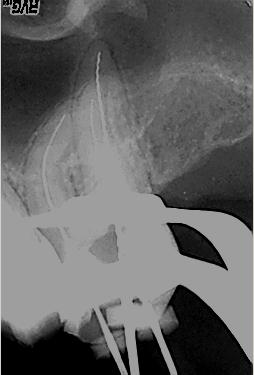

Zustand unmittelbar vor Behandlungsbeginn im Juni 2003. Die Fraktur des distalen Zahnanteils hat die Patientin jetzt zur Einwilligung in die Behandlung motiviert. Auffällig ist in dieser Projektion die besonders starke Krümmung der mb Wurzel sowie die knochennahe Defektlage distal. Es erfolgte zunächst die Kariesentfernung gefolgt von einer chirurgischen Kronenverlängerung zur Herstellung der biologischen Breite sowie Ermöglichung des sog. Ferrule-Effektes. Danach wurde der Zahn adhäsiv aufgebaut. Erst jetzt wurde mit der eigentlichen WKB begonnen

Röntgenmeßaufnahme

Röntgenmeßaufnahme nach vorgängig durchgeführter endometrischer Längenbestimmung